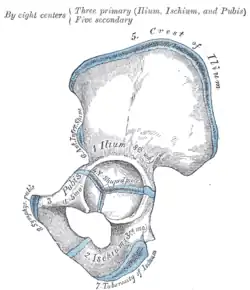

Darstellung der Ossifikation eines Hüftbeines -

Beide Hüftbeine bestehen aus je drei Anteilen:

Diese drei Knochen verschmelzen beim Menschen etwa mit dem 15. Lebensjahr im Bereich der Hüftgelenkpfanne zum nun einheitlichen Hüftbein.

Alle drei Hüftknochen treffen in der Hüftgelenkpfanne (Acetabulum) zusammen, welche mit dem Kopf des Oberschenkelknochens das Hüftgelenk bildet.